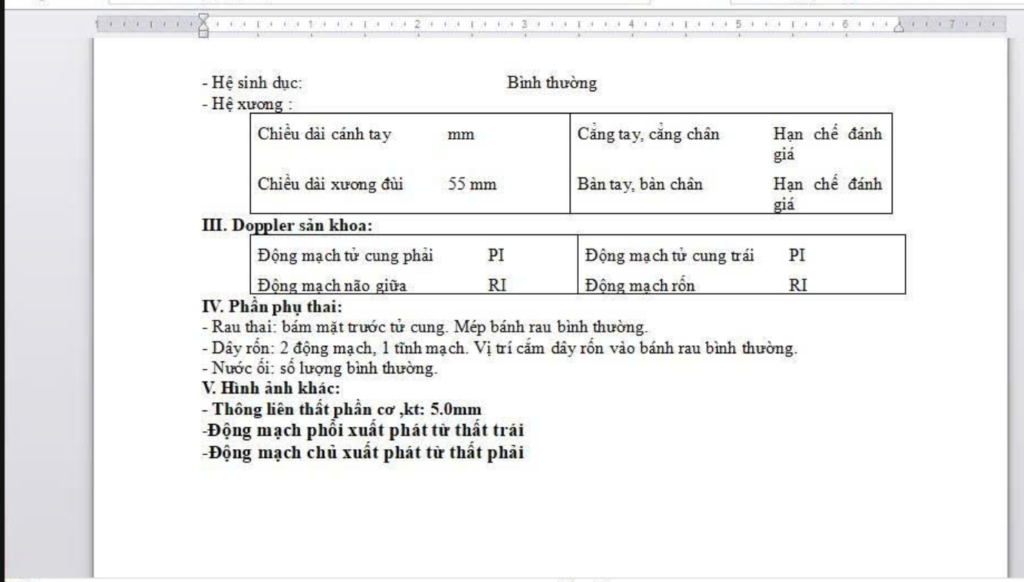

Chị H. mang thai 24 tuần đến phòng khám Dr Tú y học bào thai để siêu âm hình thái. Thai phát triển phù hợp tuổi thai, các cơ quan khác bình thường. Nhưng trong phần tim thai, bác sĩ ghi nhận một lỗ nhỏ ở vách ngăn giữa hai buồng thất.

Kết luận ghi: nghi ngờ thông liên thất phần cơ, kích thước 2 mm.

Thông liên thất phần cơ là một dạng dị tật tim bẩm sinh, trong đó có một lỗ nhỏ ở phần cơ của vách ngăn giữa hai buồng thất.

Thông liên thất phần cơ là lỗ nằm ở phần cơ dày của vách ngăn. Đây là vị trí có khả năng tự đóng cao hơn so với phần màng.

Thông liên thất phần cơ chỉ cần phẫu thuật khi lỗ thông đủ lớn để ảnh hưởng đến hoạt động của tim và phổi. Khi lỗ lớn hơn khoảng 6–7 mm, hoặc có nhiều lỗ thông liên thất phần cơ, máu từ thất trái chảy nhiều sang thất phải, làm tăng lưu lượng máu lên phổi và khiến tim phải làm việc quá mức.